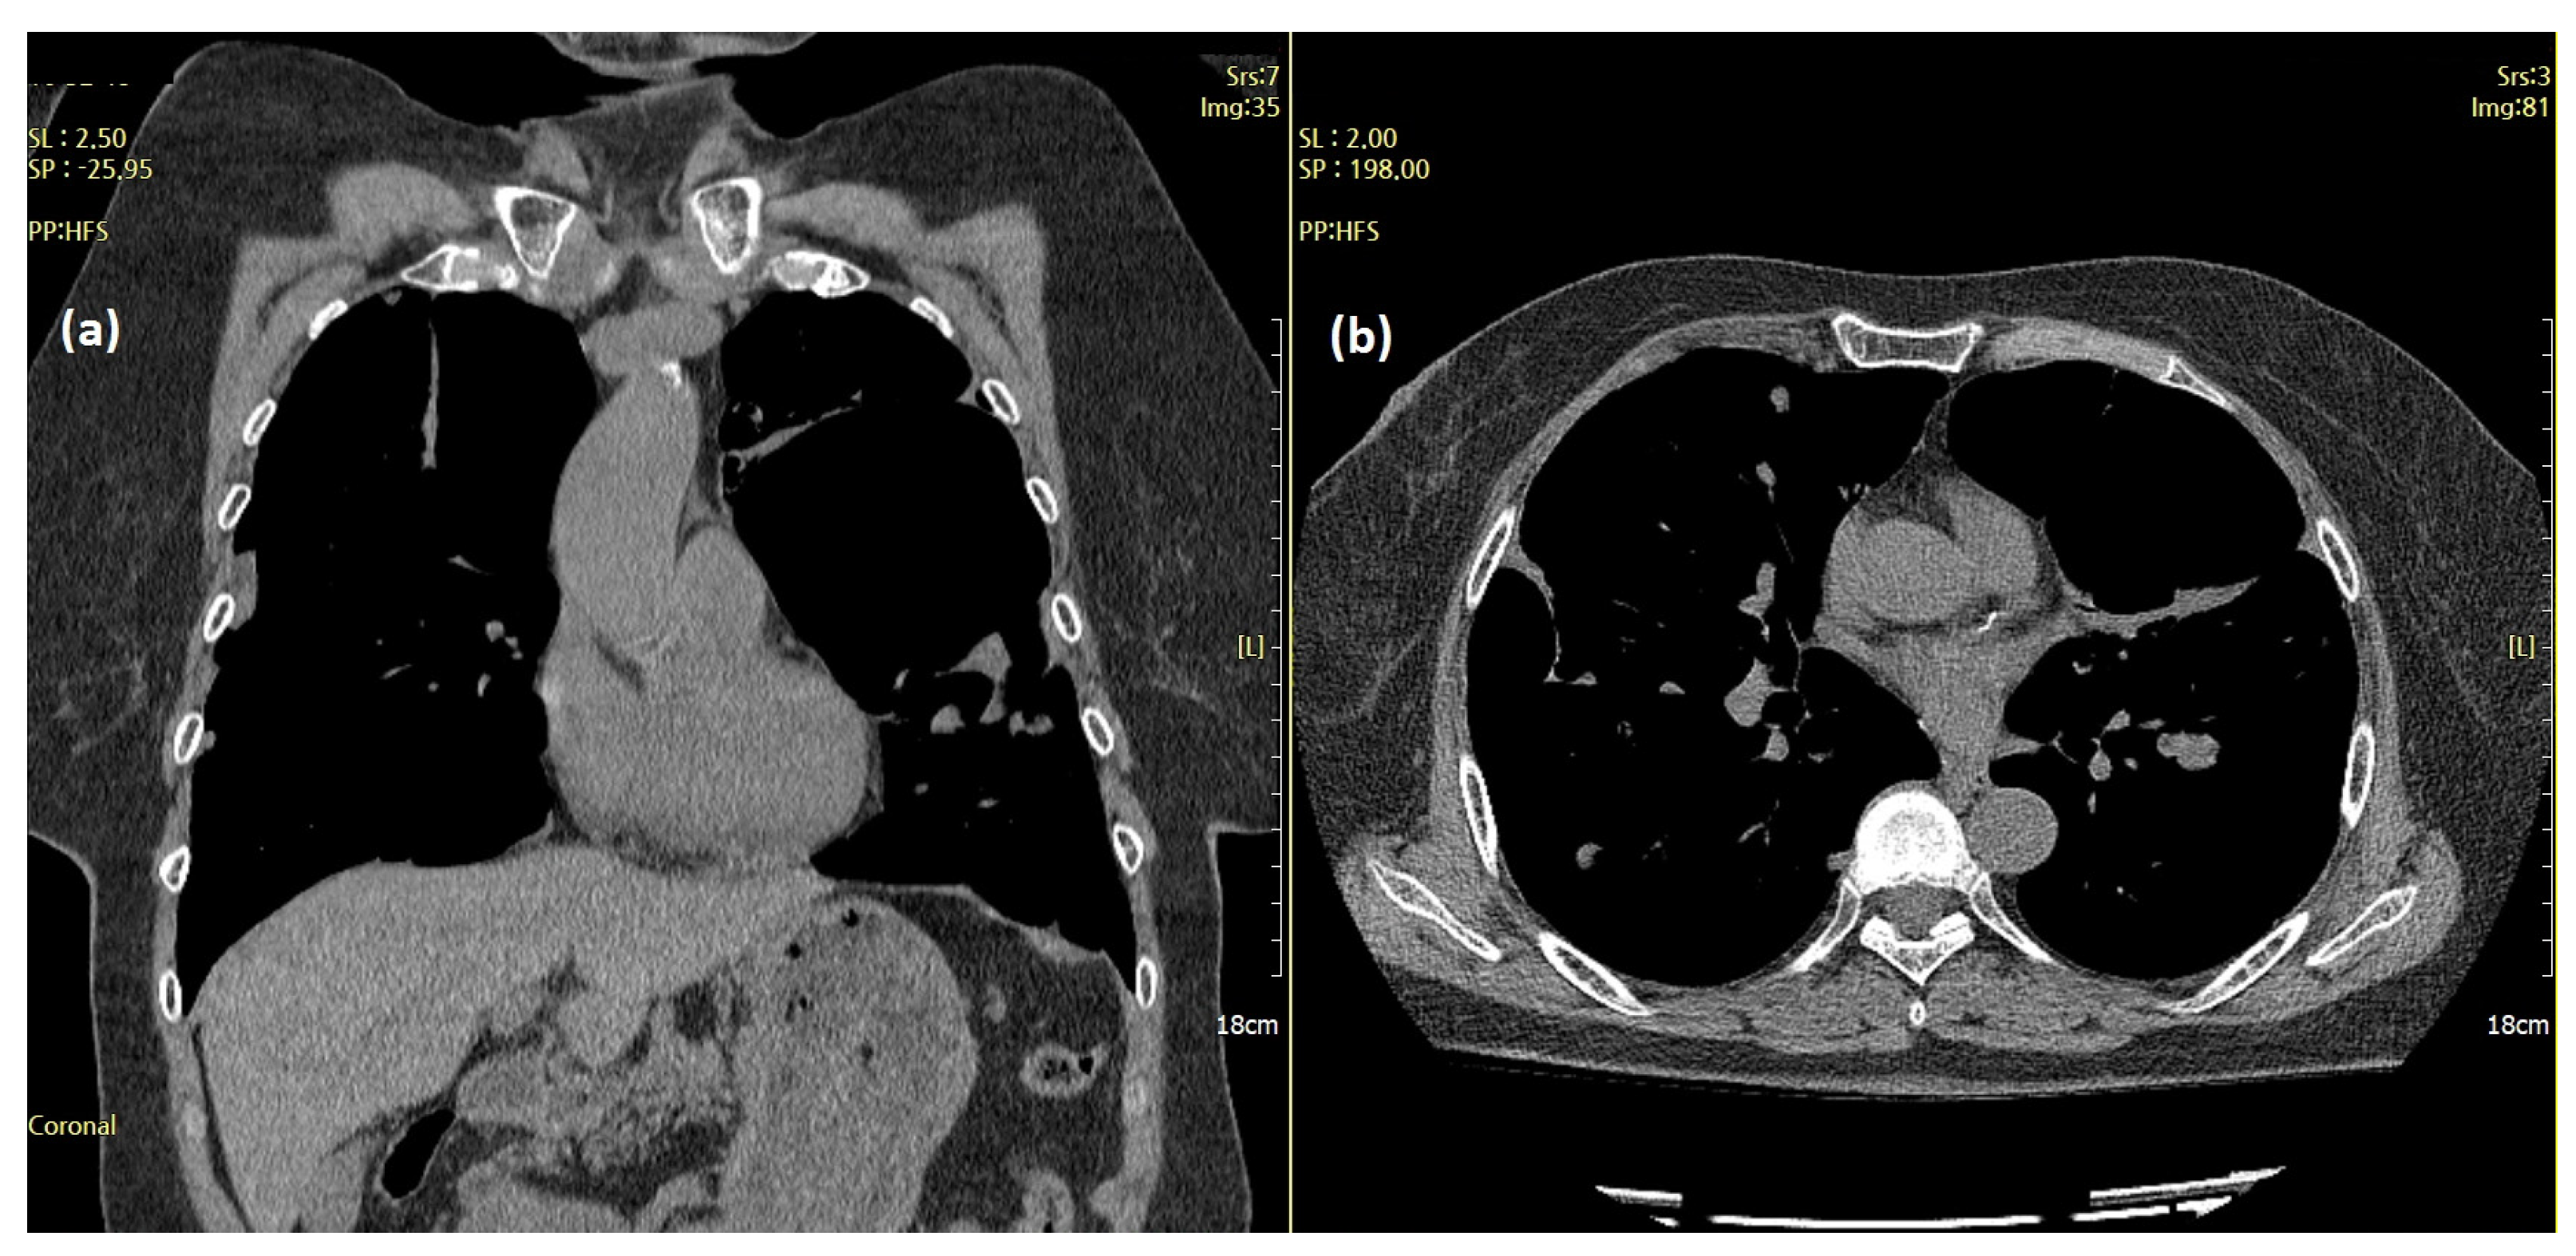

Subsequently, the patient experienced two more episodes of recurrent dyspnea owing to increased pleural effusion within the two years following the initial onset of symptoms. A chest CT performed at the time of the third hospitalization for acute dyspnea in June 2019 revealed large and multiple hydropneumothoraces and bullae with massive bilateral pleural effusions (Figure 2).

Figure 2.

Chest computed tomography (CT) features of the aggravating lesions. Cystic masses (arrow) and large and multiple hydropneumothoraces with massive pleural effusion (red circles) on chest CT (June 2019). (a) Coronal and (b) axial views.